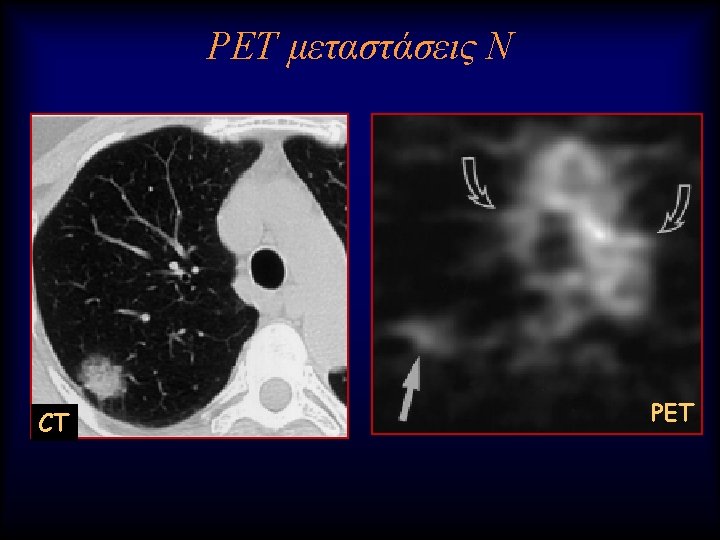

Lung nodule analysis • Evaluating Pulmonary Nodules Pulmonary nodules ≤ 4 mm have a low risk of being cancerous; • nodules between 4 -8 mm are of intermediate risk for cancer; follow up CT scans for both categories are recommended on different schedules • Pulmonary nodules >8 mm and mixed solid/ground glass nodules are suspicious for cancer; percutaneous needle aspiration biopsy (PNAB), positron emission tomography (PET), or video assisted thoracic surgery (VATS) should be considered